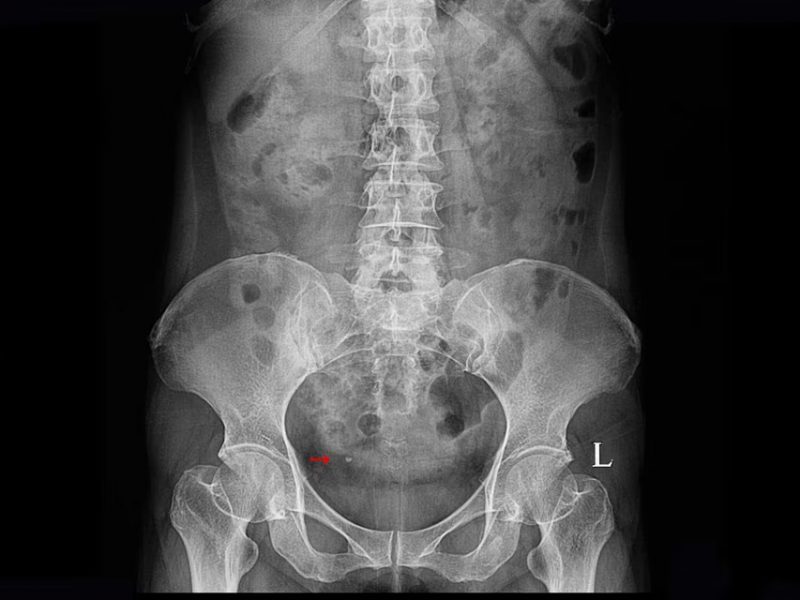

Les causes les plus fréquentes sont variées. Les infections urinaires sont responsables

d’une irritation des muqueuses pouvant entraîner un saignement. Les calculs urinaires, en

migrant dans les voies excrétrices, provoquent des lésions mécaniques. Les traumatismes

Uroscanner

L’uroscanner (ou uro-TDM) est l’examen de référence en cas d’hématurie macroscopique

inexpliquée, surtout chez les patients à risque. Réalisé avec injection de produit de

contraste, il offre une analyse complète de l’appareil urinaire, du parenchyme rénal jusqu’à la

vessie. Il est particulièrement performant pour détecter des tumeurs urothéliales, des calculs

ou des malformations anatomiques.